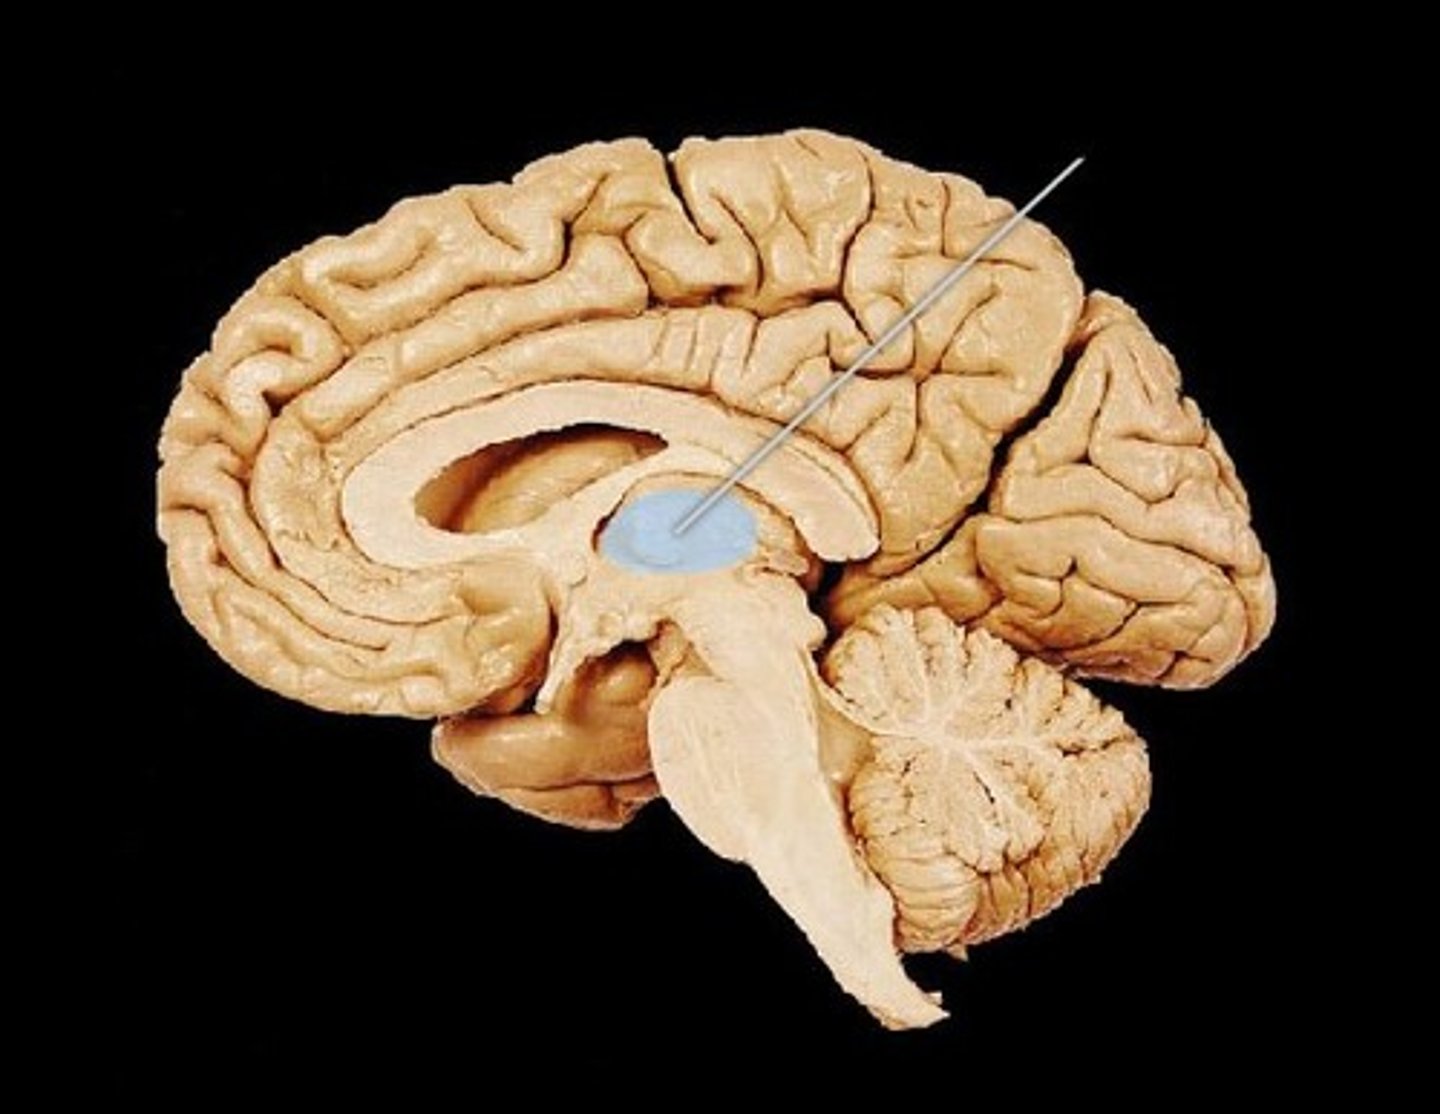

CSF circulates through

lateral ventricles to third ventricle to cerebral aqueduct to fourth ventricle to subarachnoid space and central canal of spinal cord

lateral ventricle

one of the two ventricles located in the center of the telencephalon

third ventricle

the ventricle located in the center of the diencephalon

cerebral aqueduct

connects the third and fourth ventricles

fourth ventricle

the ventricle located between the cerebellum and the dorsal pons, in the center of the metencephalon